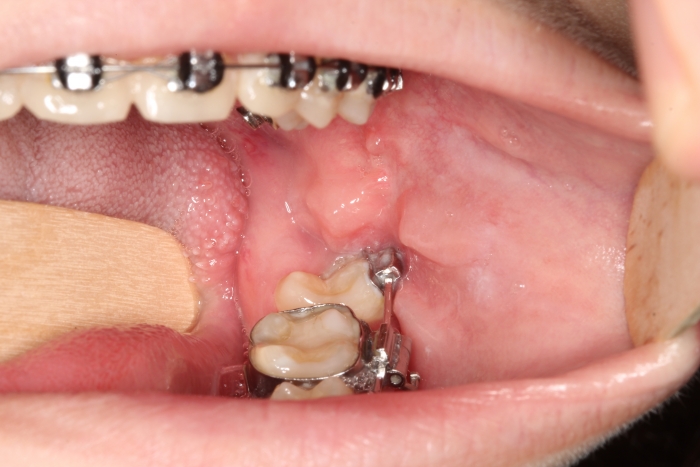

Elementos 37 e 47, respondendo bem ao tracionamento - Clínica Cliniface

Elementos 37 e 47, respondendo bem ao tracionamento